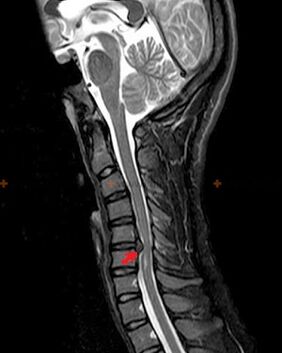

Diagnóstico e signos de raios X

A osteocondrose é un diagnóstico de raios X, xa que un cadro clínico detallado só está presente no momento da exacerbación, mentres que cando unha persoa está en completo benestar subxectivo, poden producirse cambios na columna vertebral. Sen un exame de raios X, só se pode falar dunha sospeita de osteocondrose, xa que síntomas similares tamén poden ser causados por outras enfermidades (miosite, neoplasia vertebral, etc.).

Para diagnosticar a osteocondrose utilízanse os seguintes métodos de exame: radiografía (preferentemente con probas funcionais), MSCT e resonancia magnética. Este último estudo é o máis preferible xa que permite unha visualización moi clara do estado das estruturas intervertebrais.

Os signos de raios X da osteocondrose inclúen os seguintes cambios na columna vertebral:

- Altura reducida dos discos intervertebrais.

- Presenza de crecementos óseos marxinais.

- Violación da posición das vértebras entre si.

- Deformacións de corpos vertebrales e arcos, etc.

A presenza dos cambios descritos anteriormente, así como os cambios na estrutura do disco intervertebral detectados por MSCT e resonancia magnética, serven como signos fiables da presenza de osteocondrose.